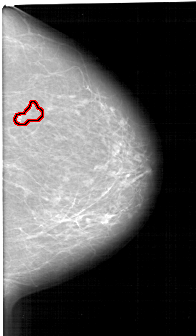

A_1349_1.RIGHT_MLO

RIGHT_MLO LINES 6046 PIXELS_PER_LINE 3286 BITS_PER_PIXEL 12 RESOLUTION 43.5 OVERLAY

FILE: A_1349_1.RIGHT_MLO.OVERLAY

TOTAL_ABNORMALITIES 1

ABNORMALITY 1

LESION_TYPE CALCIFICATION TYPE PLEOMORPHIC DISTRIBUTION SEGMENTAL

ASSESSMENT 4

SUBTLETY 4

PATHOLOGY BENIGN

TOTAL_OUTLINES 2

BOUNDARY